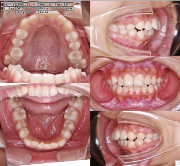

ステップ3. レントゲン (パノラマ,セファロ)撮影 口腔内写真撮影

口腔内写真,レントゲン

(必要に応じてCT)

装置装着前

装置装着後

ステップ3. レントゲン(パノラマ、セファロ)撮影・口腔内写真撮影

口腔内写真、レントゲン(必要に応じて CT )、印象(歯型)採得